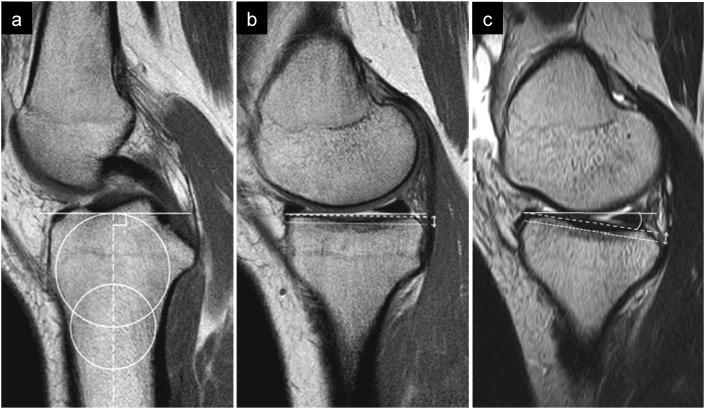

METHODS

Twenty-seven patients who underwent ACLR (group A), and 15 patients with combined MM repair (group AM) were included in the study. Anterior tibial translation (ATT) was measured under general anaesthesia just before surgery using a knee arthrometer. MRI was performed in the 10°-knee-flexed position. The MTS and MTPD were measured on sagittal view, and the CTS was measured on coronal view. These parameters were compared between the groups. Differences in MRI measurements or patient demographics between the groups were evaluated using the Mann-Whitney test.

方法

本研究纳入了27例行ACLR的患者(A组)和15例行MM联合修复的患者(AM组)。术前在全身麻醉下使用膝关节测角仪测量胫骨前移(ATT)。在膝关节屈曲10°位进行MRI检查。在矢状位视图上测量MTS和MTPD,在冠状位视图上测量CTS。对两组之间的这些参数进行比较。使用Mann-Whitney检验评估两组之间MRI测量值或患者人口统计学的差异。